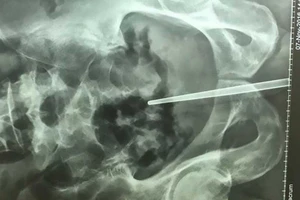

#nhét đũa vào dương vật

Chơi dại nhét đũa vào dương vật